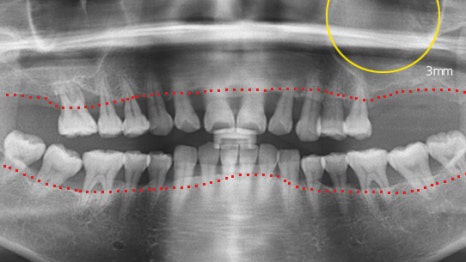

사례 2

크라운 치료를 통한 자연치아 보존

잇몸뼈가 약해 12개 임플란트를 권유받았던

환자분께 치주 치료를 진행한 결과,

전치부(앞니) 잇몸 상태가 개선되어 발치하지 않고

크라운 치료로 복원하였습니다.

어금니에는 6개만 식립하여 기능을 되살렸습니다.